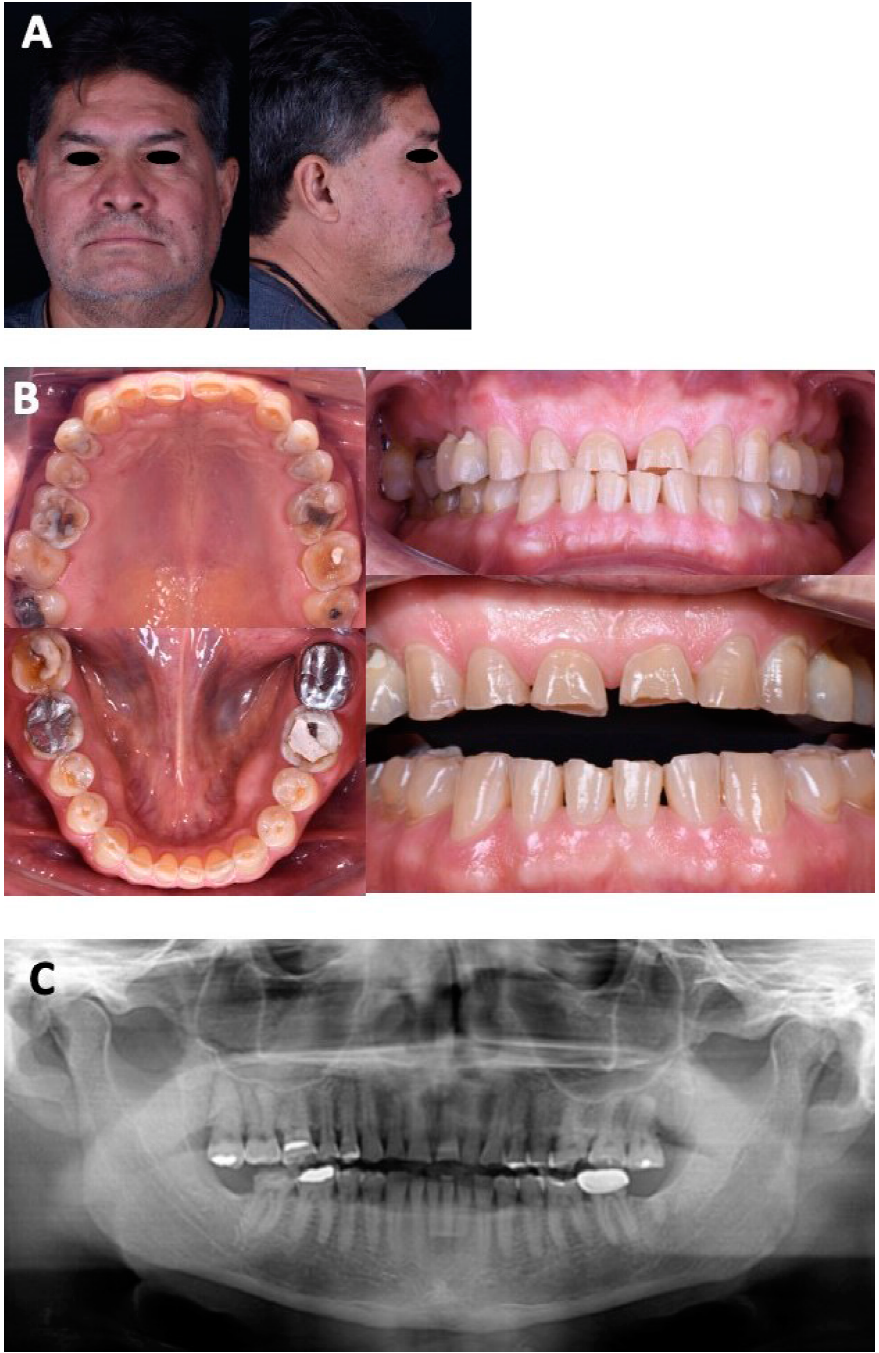

Paciente masculino de 60 años, su motivo de consulta: “Necesito muchos arreglos”, refierió ser diabético tipo II, con tratamiento de metformina. En el análisis extraoral presentó un biotipo facial mesocefálico. La línea interpupilar coincide con la línea intercomisural. La línea media facial mostró armonía. El tercio facial superior se encuentra disminuido mientras que el tercio medio e inferior son equivalentes. El tercio facial inferior, es dos veces mayor que el tercio superior y son simétricos, lo cual cumple con la norma de valores de análisis estético (Tabla 1; Figura 1 A). El paciente presenta bruxismo del sueño y de vigilia con etiología multifactorial.

Figura 1 Estudios iniciales. A. Fotografías faciales iniciales de frente y perfil. B. Fotografías intraorales iniciales. C. Ortopantomografía.

En el análisis intraoral presentó arcos cuadrados en ambas arcadas y presencia de torus mandibulares, banda ancha de encía queratinizada generalizada en todos los sextantes. En el arco maxilar se observó exposición radicular de los dientes 17,16, 15, 14, 26 y 27, así como restauraciones defectuosas en los dientes 14-18, y 24-28, pérdida de sustancia dental en todos los dientes incluyendo sector anterior haciendo énfasis de abfracciones en dientes 24 y 25.

Además, se identificaron restauraciones defectuosas en dientes 35-37, 46 y 47, así como pérdida de sustancia dental en todos los dientes de la arcada mandibular, remarcando las abfracciones de los 4 premolares (Figura 1B). En la ortopantomografía se observaron los senos maxilares permeables y un correcto paralelismo radicular, ausencia de los dientes 38 y 48, así como ausencia de crestas óseas (Figura 1C).

En el análisis oclusal, se observó relación canina y Clase I molar, sobremordida vertical 1mm y sobremordida horizontal 1mm, la DVO 61 y dimensión vertical en reposo (DVR) 66, el espacio libre interoclusal es de 5mm y la discrepancia entre máxima intercuspidación y relación céntrica es de 0.5mm (Figura 2A).